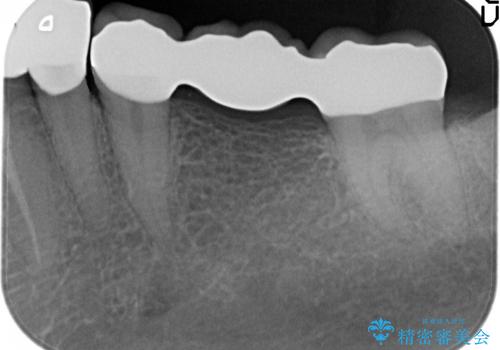

- 左下の銀歯を前の歯に合わせて白くしたいといらっしゃった方の症例です。

前歯部のシェードに合わせ、左下4及び左下567ブリッジをオールセラミッククラウンにて補綴しました。

今回用いたオールセラミッククラウンはジルコニアフレームという白い素材の上にセラミックを盛っているため、審美性が非常に高いのが特徴です。

また、ジルコニアは人工ダイヤモンドの材料にも使われているほど高い強度を持っており、そのためオールセラミッククラウンは審美性だけでなく、奥歯やブリッジの補綴も可能とするクラウンです。